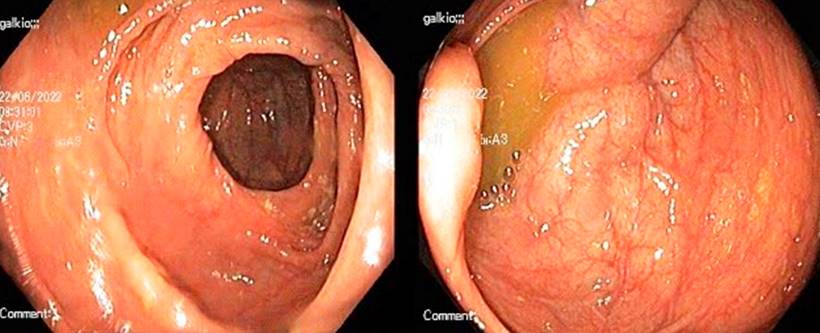

After 6 months, his respiratory and constitutional symptoms improved, but he was admitted to the hospital due to persistent abdominal pain and diarrhea. Adherence to antituberculous therapy was confirmed, and microbiological studies for TB were negative. The laboratory tests detected fecal calprotectin of 2,060 μg/g (Table 1) and the magnetic resonance enterography (MRE), intestinal sub-occlusion in the ileum (Figure 1). A new ileocolonoscopy identified cecal folds, appendiceal orifice, and ileocecal valve with severe edema covered by ulcers, easy bleeding, and edema involving the proximal ascending colon. In addition, biopsies were taken that reported inflammatory bowel disease with chronic ulceration and granulomas (Figure 2). The diagnosis of CD was made with a Crohn’s disease activity index (CDAI) of 421 points. Controversially, corticosteroids were postponed, starting treatment with azathioprine.

A month later, he consulted for abdominal pain, so a new CT scan was performed, which reported enteritis in the jejunum, pneumoperitoneum, and collections. He was taken to a laparotomy, noting obstruction of the proximal and distal small intestine, granulomas in the middle of the small intestine, perforation of the middle jejunum with a plastron that compromised the distal ileum, and a fistulous tract. An intestinal resection and anastomosis were performed. Once TB treatment was completed, biological therapy was started with adalimumab up to a maintenance dose of 40 mg subcutaneously every 2 weeks. The clinical evolution was favorable; 1 year later, he attended an outpatient gastroenterology check-up on clinical remission and without complications, and a new colonoscopy showed no alterations (Figure 3).